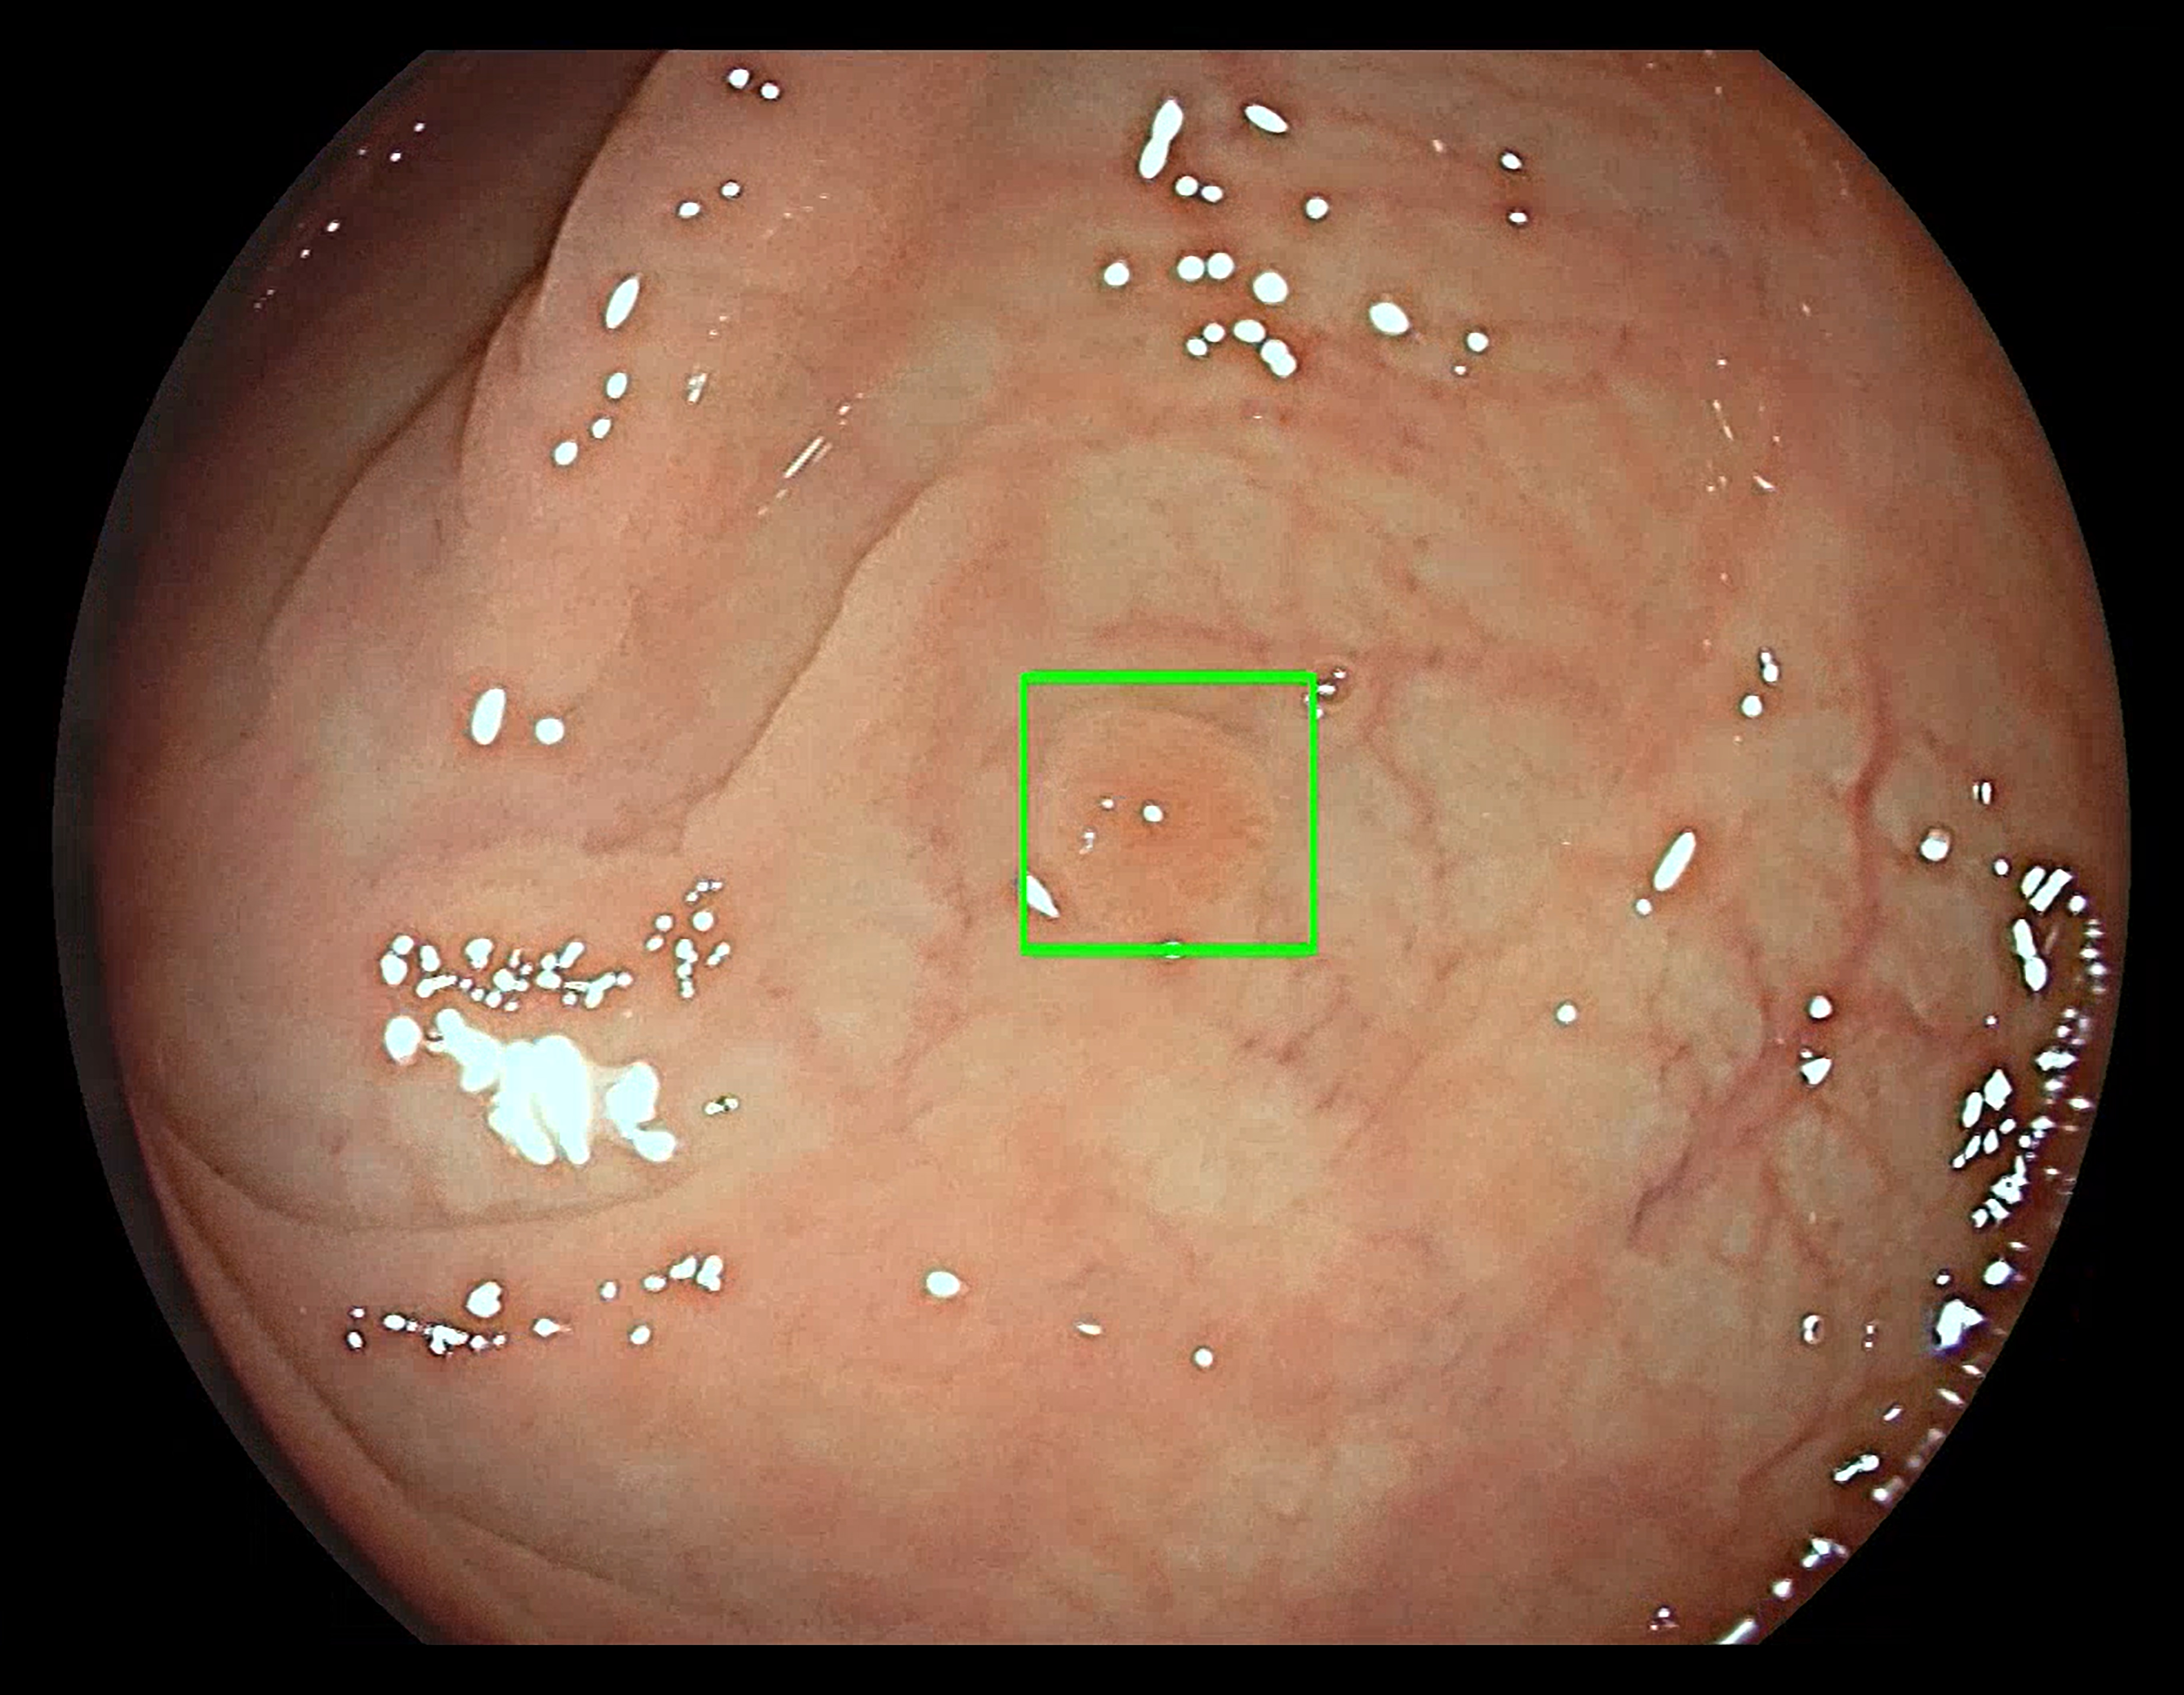

The GI Genius module uses advanced artificial intelligence to highlight the presence of pre-cancerous lesions with a visual marker in real-time – serving as an ever vigilant second observer. Studies have shown that having a second observer can increase polyp detection rates; every 1 percent increase in adenoma detection rate reduces the risk of colorectal cancer by 3 percent.1 Colorectal cancer (CRC) is the third most common form of cancer globally with 1.8 million new cases every year.2

“One of the key factors to maximizing the prevention of colorectal cancer is the integration of advanced technologies like artificial intelligence into daily practice. The use of artificial intelligence in gastroenterology ushers in a new era of diagnostic endoscopy that can improve the quality of colonoscopies. In my experience, the GI Genius module can be extremely precise in identifying lesions in the colonic mucosa that can be difficult to detect and may have been missed. This change in daily practice has the potential to improve diagnosis and overall outcomes for patients that may have colorectal cancer,” said Prof. Alessandro Repici, head of gastroenterology at Humanitas Hospital in Rozzano (Milan).

“Medtronic is focused on preventing colorectal cancer by early detection of pre-cancerous polyps with AI-assisted technologies,” said Giovanni Di Napoli, vice president and general manager of the Gastrointestinal & Hepatology business, which is part of the Minimally Invasive Therapies Group at Medtronic. “The GI Genius module automatically detects polyps, including small flat polyps that may go undetected thus increasing accuracy and reducing the risk of interval cancers which can occur between colonoscopies.”